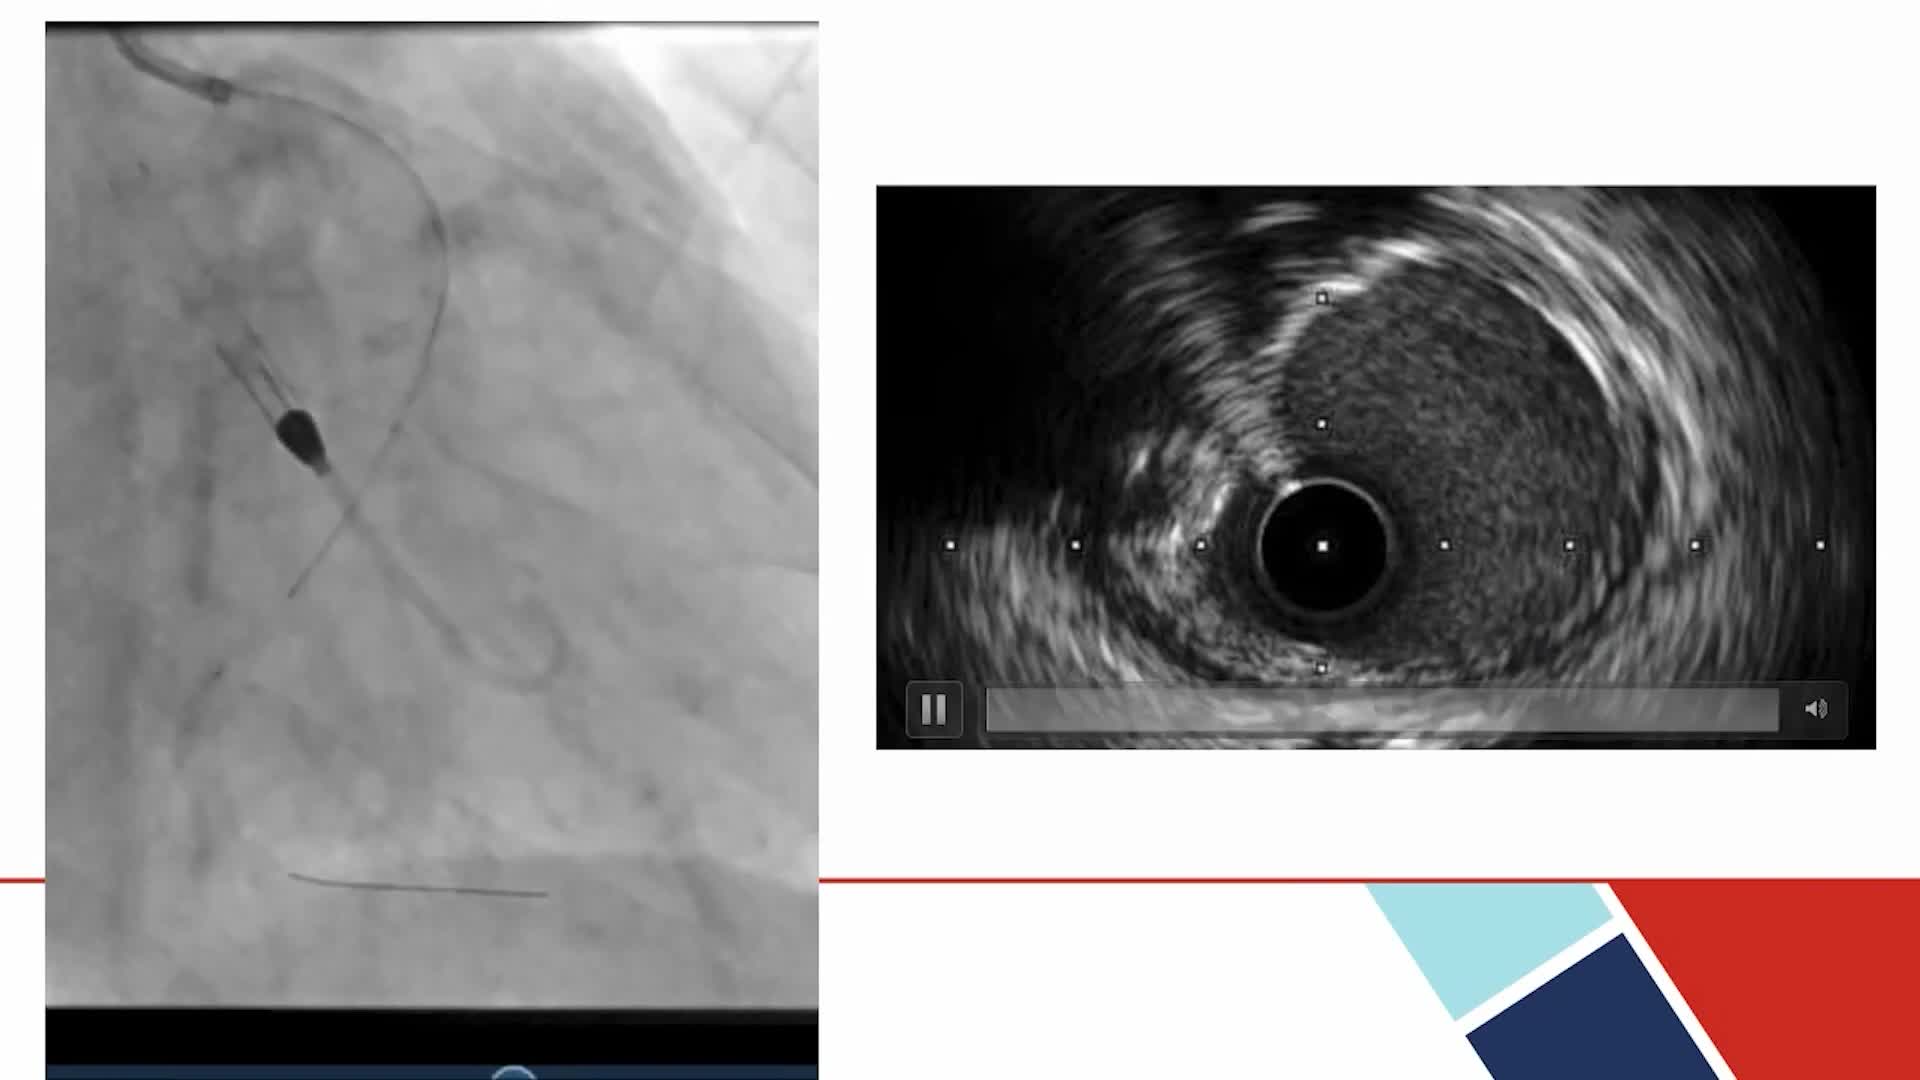

Calcium Characteristics by Gender - What Does the Imaging Show? Disrupt CAD Pooled OCT Analysis

- Calcium Modification

- Intracoronary Imaging